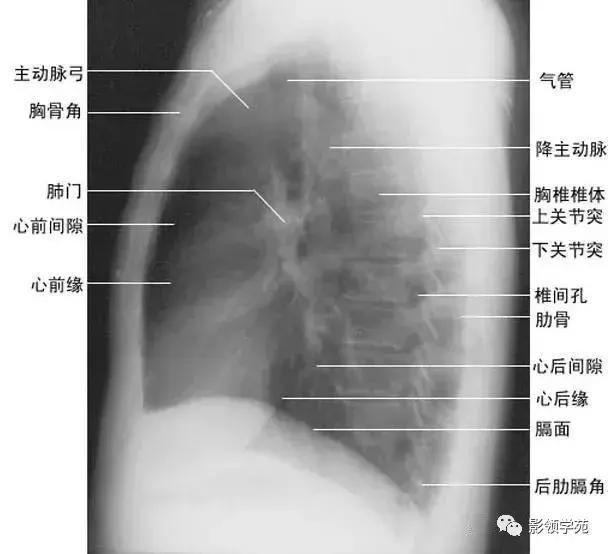

1、斜裂 一般在正位片上不能显示.在侧位片上表现为自后上斜向前下的线条状阴影:右德斜裂的后端起始于第4、5胸椎水平,斜向前下方走行,止于膈面距前缘2~3cm处,与膈顶部的水平面约成50°角;左侧斜裂后端起始点较右侧稍高,在第3~4后肋端水平,因而其倾斜度也较右饲稍大,前下端达肺的前下角处,与膈顶水平面约成60°角。叶间胸膜面通常略有弯曲,斜裂上半部稍斜向外,下半部稍斜向内,故在侧位片上可成s形。

2、横裂又称水平裂,约70%的人正、撼位胸片均可显影。在正位片上表现为右中肺野横行细线状阴影,从第6肋腋部水平自外向内延伸.并止于肺门外lcm处。可向上或向下倾斜10:左右或略成曲线;在侧位片上,横裂起白斜裂中部,向前呈水平方向走行达前胸壁。其位置的改变可作为判断肺体积变化的标志(如上图)。

2、侧位肺门 侧位胸片上,两饲肺门阴影大部分重叠,若以侧位气管轴线为界,右肺门略信其前下,左肺门大部分在其后上。侧位肺门影前缘为右上肺静脉干形成的椭圆形阴影,前后径为2cm左右;中间纵行透亮区为气管及气管分叉,其内圆形透亮影表示支气管开口,右侧在上,左侧居下;后上缘为左肺动脉弓,下缘由两下肺动脉构成下行的树枝状影。因此,侧位肺门影似一尾巴拖长的“逗号”(如上右图):

标准右前斜位(又称第一斜位)为后前位向左旋转约45。所得影像。心前缘自上而下由主动脉弓曼升主动脉、肺动脉、右心室漏斗部、右心室前壁和左心室下端构成。升主动脉前缘平直,弓部则在上方弯向后行;肺动脉段和漏斗部稍为隆起;心尖以上大部分为右心室构成。心前缘与胸壁之间有尖向下的三角形透明区称为心前间隙。心后缘上段为左心房,下段为右心房,两者无清楚分界。心后缘与脊柱之间透明区称心后间隙,食管在心后间隙通过,钡剂充盈时显影。右前斜位主要观察右室流出道及左心房大小(如下图)。

(四)左侧位

心影从后上向前下倾斜,心前缘下段为右心室前壁,上段则由右心室漏斗部与肺动脉主干构成,再苣上为升主动脉前壁,直向上走行。这些结构与翦髓壁之间的三角形透亮区称为胸骨后区。心后缘上中段由左心房构成,下段则由左心室构成。心后下缘、食管与膈之间的三角形间隙,为心后食管前间隙(如下图)。